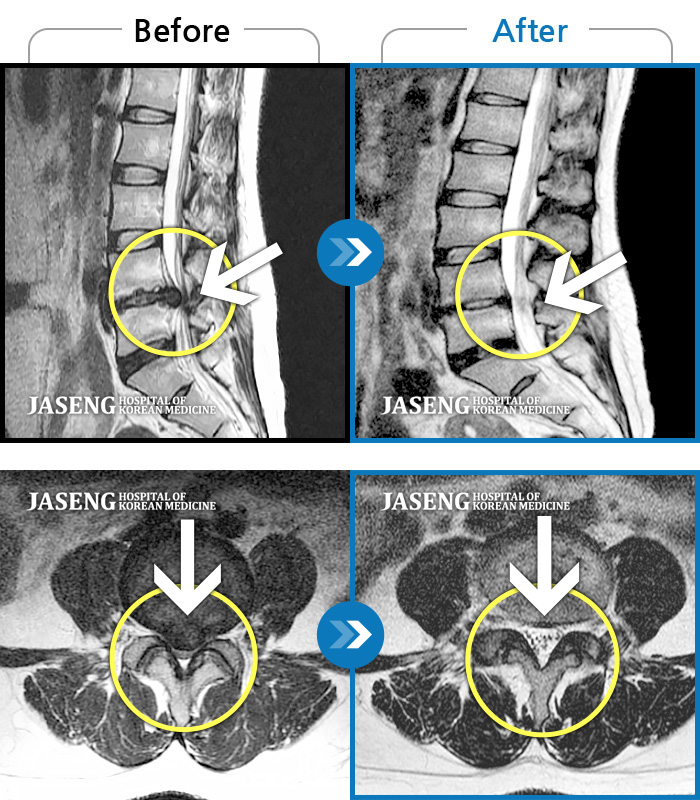

허리디스크

인천 · 조남훈 원장

허리가 너무 아프고 다리가 저려요.

촬영시기

2018.04.23 ~ 2025.12.05

2025.12.19